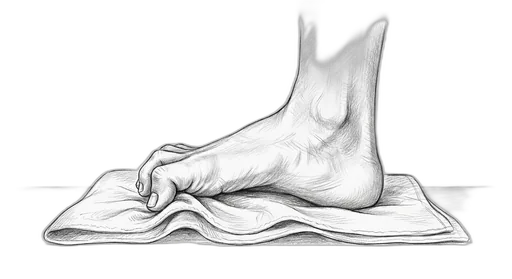

Towel Curl

This exercise strengthens the small muscles on the bottom of your foot — called the intrinsic foot muscles. These are the muscles that support your arch from the inside, kind of like a built-in orthotic. When they're strong, they help distribute your body weight more evenly, protect against overpronation (your foot rolling inward too much), and take stress off the plantar fascia, tendons, and joints.

What to expect: You may not feel dramatic changes in the first few weeks, but stick with it — these small muscles take time to build. By 6–8 weeks, many patients notice better arch support, less foot fatigue at the end of the day, and improved balance. The research shows measurable strength gains by 4–6 weeks.

How to do it: Sit in a chair with your bare feet flat on the floor. Lay a small towel flat under your foot. Curl your toes to scrunch the towel toward you — like you're trying to pick it up with your toes — then spread your toes flat and repeat. Try to use all five toes, not just the big one.